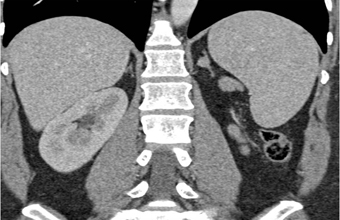

The most likely syndrome associated with the left adrenal nodule is?

Cushing’s Syndrome

Conn’s Syndrome

Turner’s Syndrome

McCune Albright Syndrome